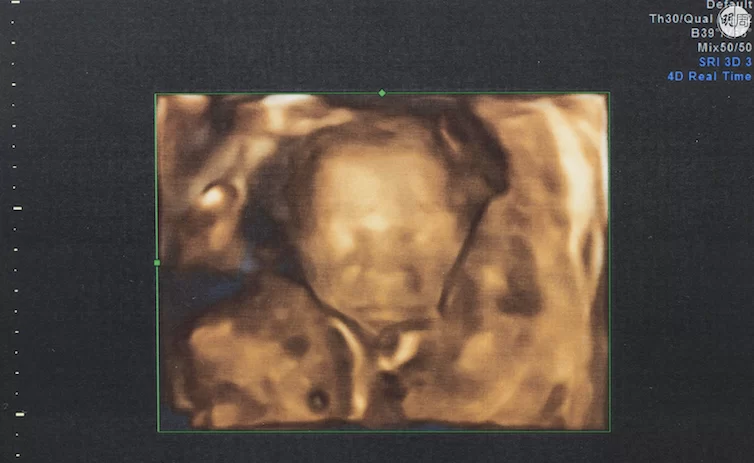

Ethan的3D結構圖,只見他睡得安穩,怎也料不到他吸收營養已出現問題。